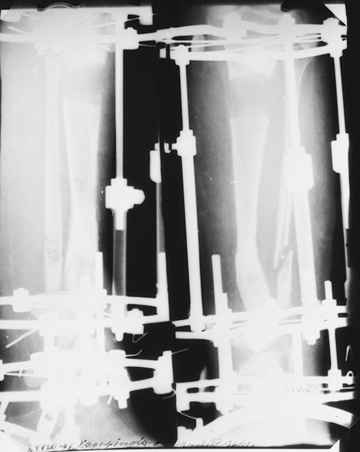

Случай, который я представляю, был сделан мной около 20 лет назад в Кургане.

Женщина 28 лет, пошедшая 13 предыдущих оперативных вмешательств по-поводу ВПБ имела 9 см. укорочения.

На первом этапе аппаратом Илизарова закрыто устранена деформация голени.

На втором этапе произведёно освежение краёв костных фрагментов б/б и м/б костей с приданием проксимальному фрагменту б/б кости впалой, а дистальному выпуклой формы, открытие канала проксимального фрагмента и погружной остеосинтез, а также остеотомия б/б кости в в/3 и м/б кости на границе с/3 и н/3 голени. Больной проводился одновременный бифокальный компрессионно-дистракционный остеосинтез. Достигнуто 11 см. удлинение и сращение ВПГ.

Срок лечения 11 месяцев. Наблюдение 2 года.